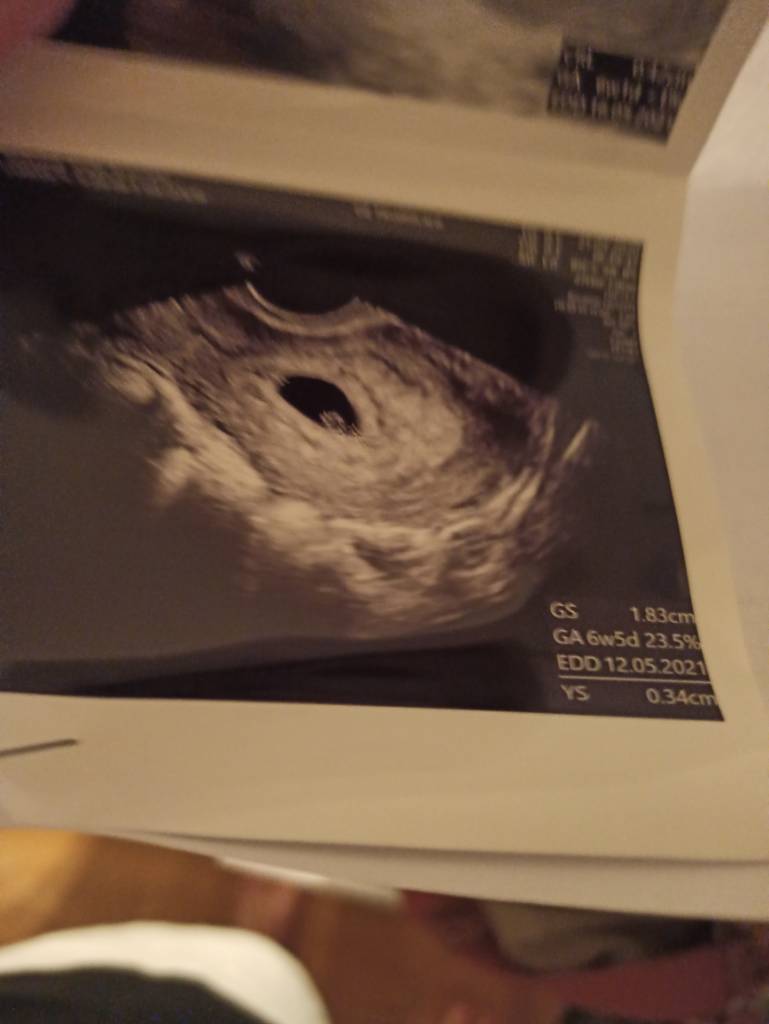

Super!!! Bardzo się cieszęJa po wizycie. Jest zarodek i jest echo [emoji3531][emoji3531]

Jestem przeszczęśliwa. Wg USG wychodzi termin na 16.05 Zobacz załącznik 1179073